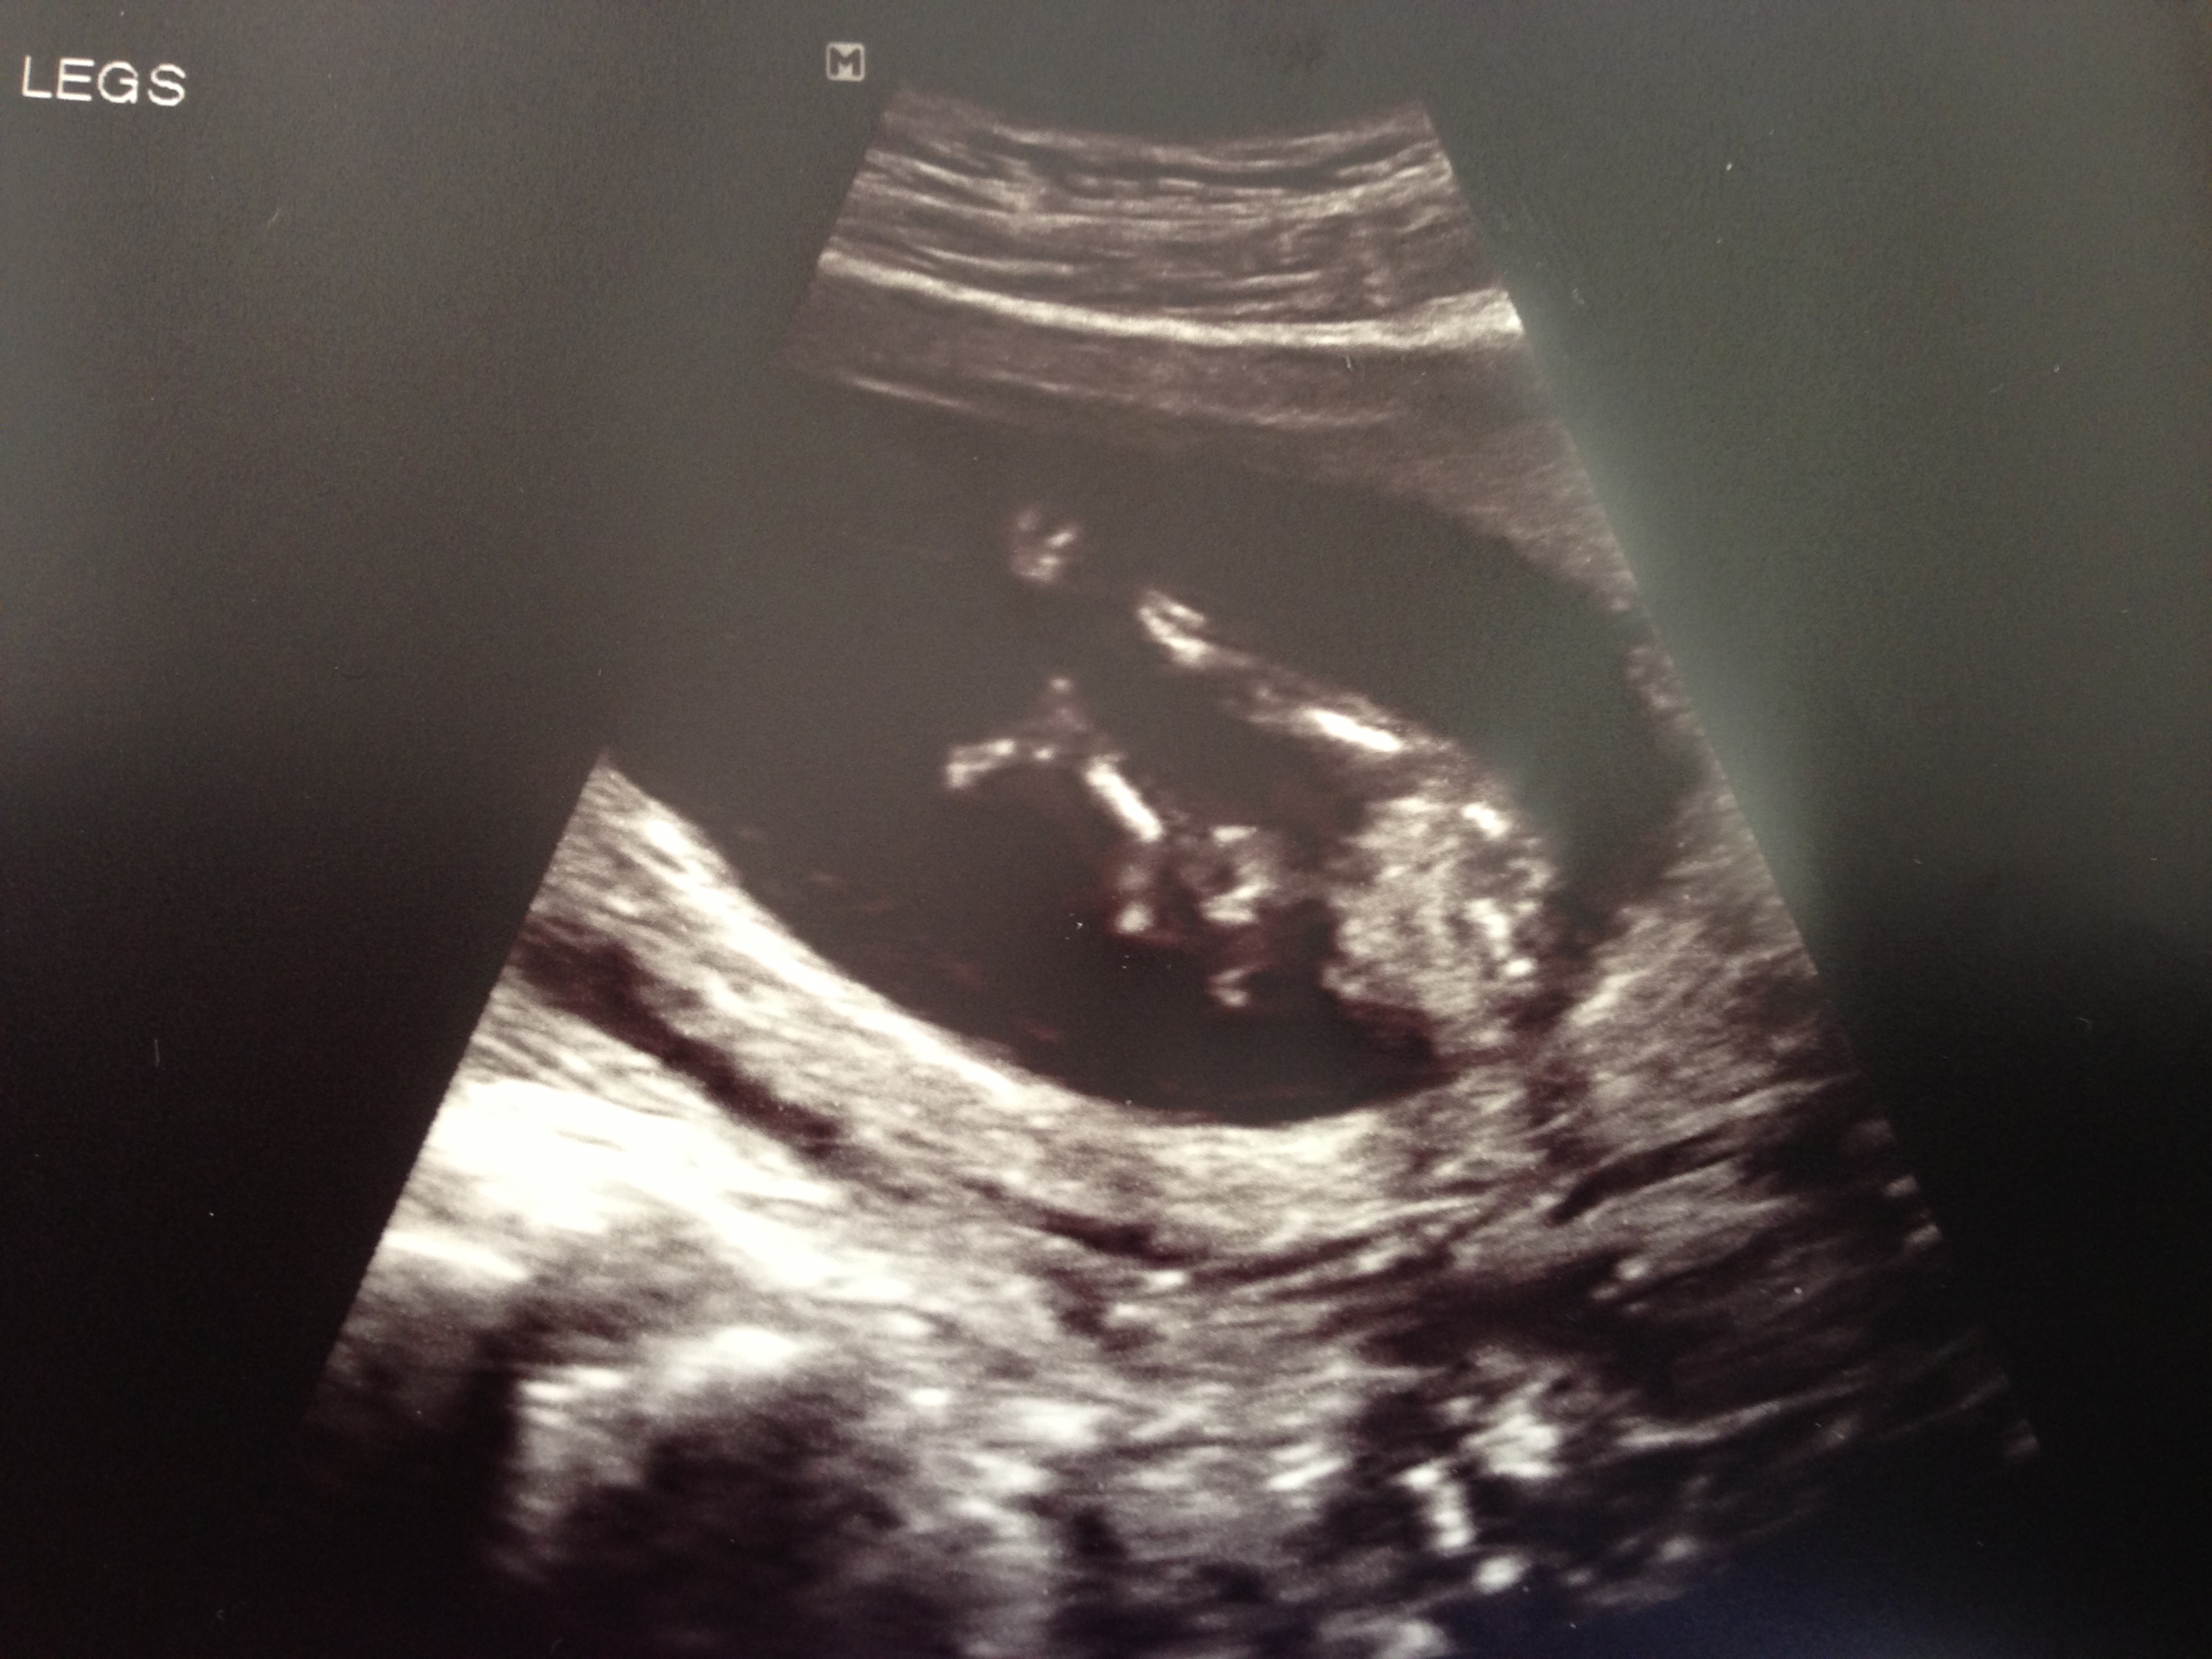

(I also posted a potty shot. Pics taken 12w4d)Attachment 13260Attachment 13260Attachment 13261

Looks like a boy nub. Not cord.

Possibly boy nub

That's not cord! Tech was lying! Cord insert is in/on the belly, not that low! And sorry but that's a little guy.

Boy nub, I'd prepare to hear boy xx

Looks like a boy nub to me,...

High risk dr friend just confirmed that's not a nub! Either cord or piece of debris. She can't quite tell but said its not in right spot to be a nub. She is 100% sure. :)

It's in the right spot. Cord looks like 3 lines floating away from the body or hovering around. That is exactly where a nub sits. Google boy nub.

I just don't agree with her at all. A quick google will show you hundreds of images of boy nubs and where it sits on the body. It may be a girl but my *guess* is boy.

A clear boy nub. Sorry it's not what you wanted to hear

Perfect boy nub. Congratulations xx

I am going with boy too, Looks like a boy nub. I hope we are all wrong and you hear pink!

Looks like a boy nub to me as well.